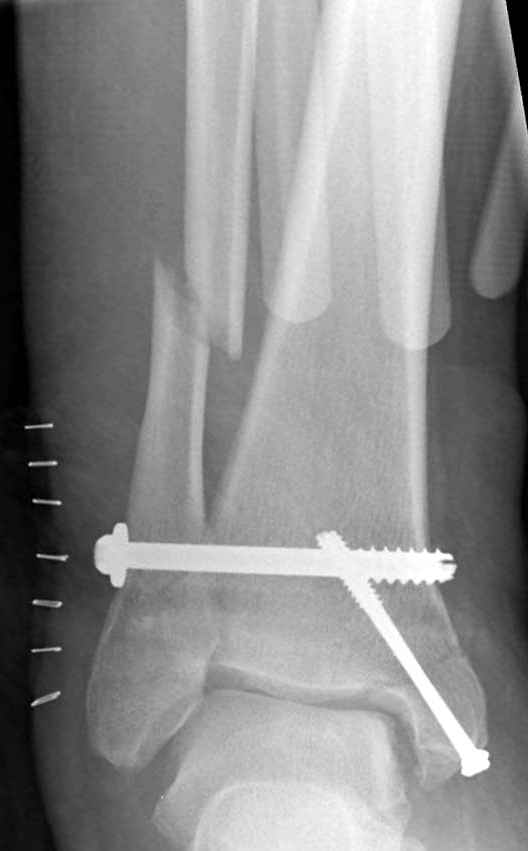

Если до сих ничего не сделано, с артродезом сустава в данный момент я бы повременил, на выставленных январских снимках хорошо сохранившийся сустав, а в "мортиз" (трехчетвертной) и на боковых снимках не менее 5 мм укорочение малоберцовой кости. Косые переломы лучше фиксировать пластинами, как то мы разбирали случай, где было отмечено, что это закон "таранная кость всегда следует за малоберцовой".

В данном случаи я бы уговорил больного на реконструкцию, для этого после удаления шурупов, спереди очистить от рубцов синдесмоз, несросшуюся наружную лодыжку - остеотомия по линии перелома и компрессирующий (lagging technique) кортикальный шуруп 3.5 мм по поперечнику остеотомии. Следующий этап - восстановление длины малоберцовой за счет удлинения, сделать поперечную остеотомию где-то на уровне сантиметр выше вашего синдесмозного шурупа, наложить длинную пластинку, прикрепить пластину за дистальный конец двумя или тремя шурупами; сохраняя контакт пластины с костью, имеющимся

compression&tension device AO system (при отсутствии любой lamina spreader подойдет, создать дистанцию между пластиной и шурупом, проведенным проксимальнее пластины) толкая проксимальный отдел пластины, низвести пластину, мортиз рентгенограмма подскажет на сколько. Если заранее сделать предоперационный план (ренгенограмма другой стороны), тогда точно можно определить, на сколько вам необходимо сделать поперечную остеотомию малоберцовой кости, для закрытия создавшегося дефекта.

Убедившись, что желаемая длина восстановлена, окончательная фиксация пластины, при этом через пластину пару 3.5 мм шурупов на синдесмоз, предпочтительно в четыре кортекса и оставить на 3 мм длиннее, если под нагрузкой синдесмотический шуруп сломается, сломанный конец легче удалить с медиальной стороны.

Медиальная сторона не в нагрузочной зоне, и там большая дыра - если есть 2.7 мм шурупы, или пару спиц в ваших условиях или методика Лазарева. Необходимо уделить внимание к мягким тканям, обнажается кость с латеральной стороны и у места где проводится остеотомия.

Недавний случай, больной 56 лет получил политравму в Англии, после переведен в США, где его успешно лечил местный ортопед, огромная статья в газете об успешной операции, своеобразный пиар, из-за того, что больной был американский пожарник на пенсии, и за его переезд было заплачено международным пожарным союзом, короче по другим показаниям перевели больного в наш университетский госпиталь.

После 5-6 недели после травмы сделана повторная операция, обошлись без удлинения малоберцовой.